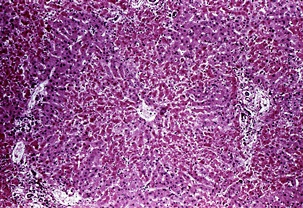

황달이란? (jaundice)

몸에 필요한 황색의 담즙색소 (빌리루빈)이 과도하게 쌓여 눈동자나 피부 등에 착색되는 현상을 말한다고 합니다. 이 담즙색소는 체내에 들어온 물질들이 분해되는 과정에서 생성되는 필요 없는 물질인데요. 일반적으로는 간에서 해독작용을 거친 후에 담즙으로 배설이 되는 것이 정상적이지만, 그렇지 못한 경우 황달이 발생하게 된다고 합니다.

황달의 원인

황달이 생기는 이유는 담즙색소라고 알려진 빌리루빈이 과도하게 생기기 때문입니다. 빌리루빈은 우리 몸의 오래된 적혈구가 파괴되면서 생기는 물질인데요. 이 물질은 담즙에 녹아서 우리 몸의 배설물과 함께 배출이 되는 것이 정상적이지만 빌리루빈의 과잉생산이나, 간의 장애, 간세포나 담도의 손상에 의해 빌리루빈이 역류할 경우 발생된다고 합니다.